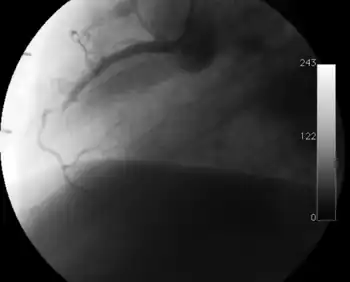

Coronary angiography

Surveillance is performed by regularly repeating coronary angiography in the cardiac catheterization laboratory, the diagnostic test of choice.[2] This is typically performed annually for the first five years after transplantation.[8] Angiography in CAV characteristically demonstrates diffuse stenoses in large coronary arteries and a reduced number of smaller coronary arteries, also known as "peripheral pruning".[2][6] However, because CAV frequently affects the entire length of the coronary artery, CAV may not be apparent by angiography alone.[2]

Partial occlusion of the left anterior descending artery on routine follow-up 8 months after transplantation.